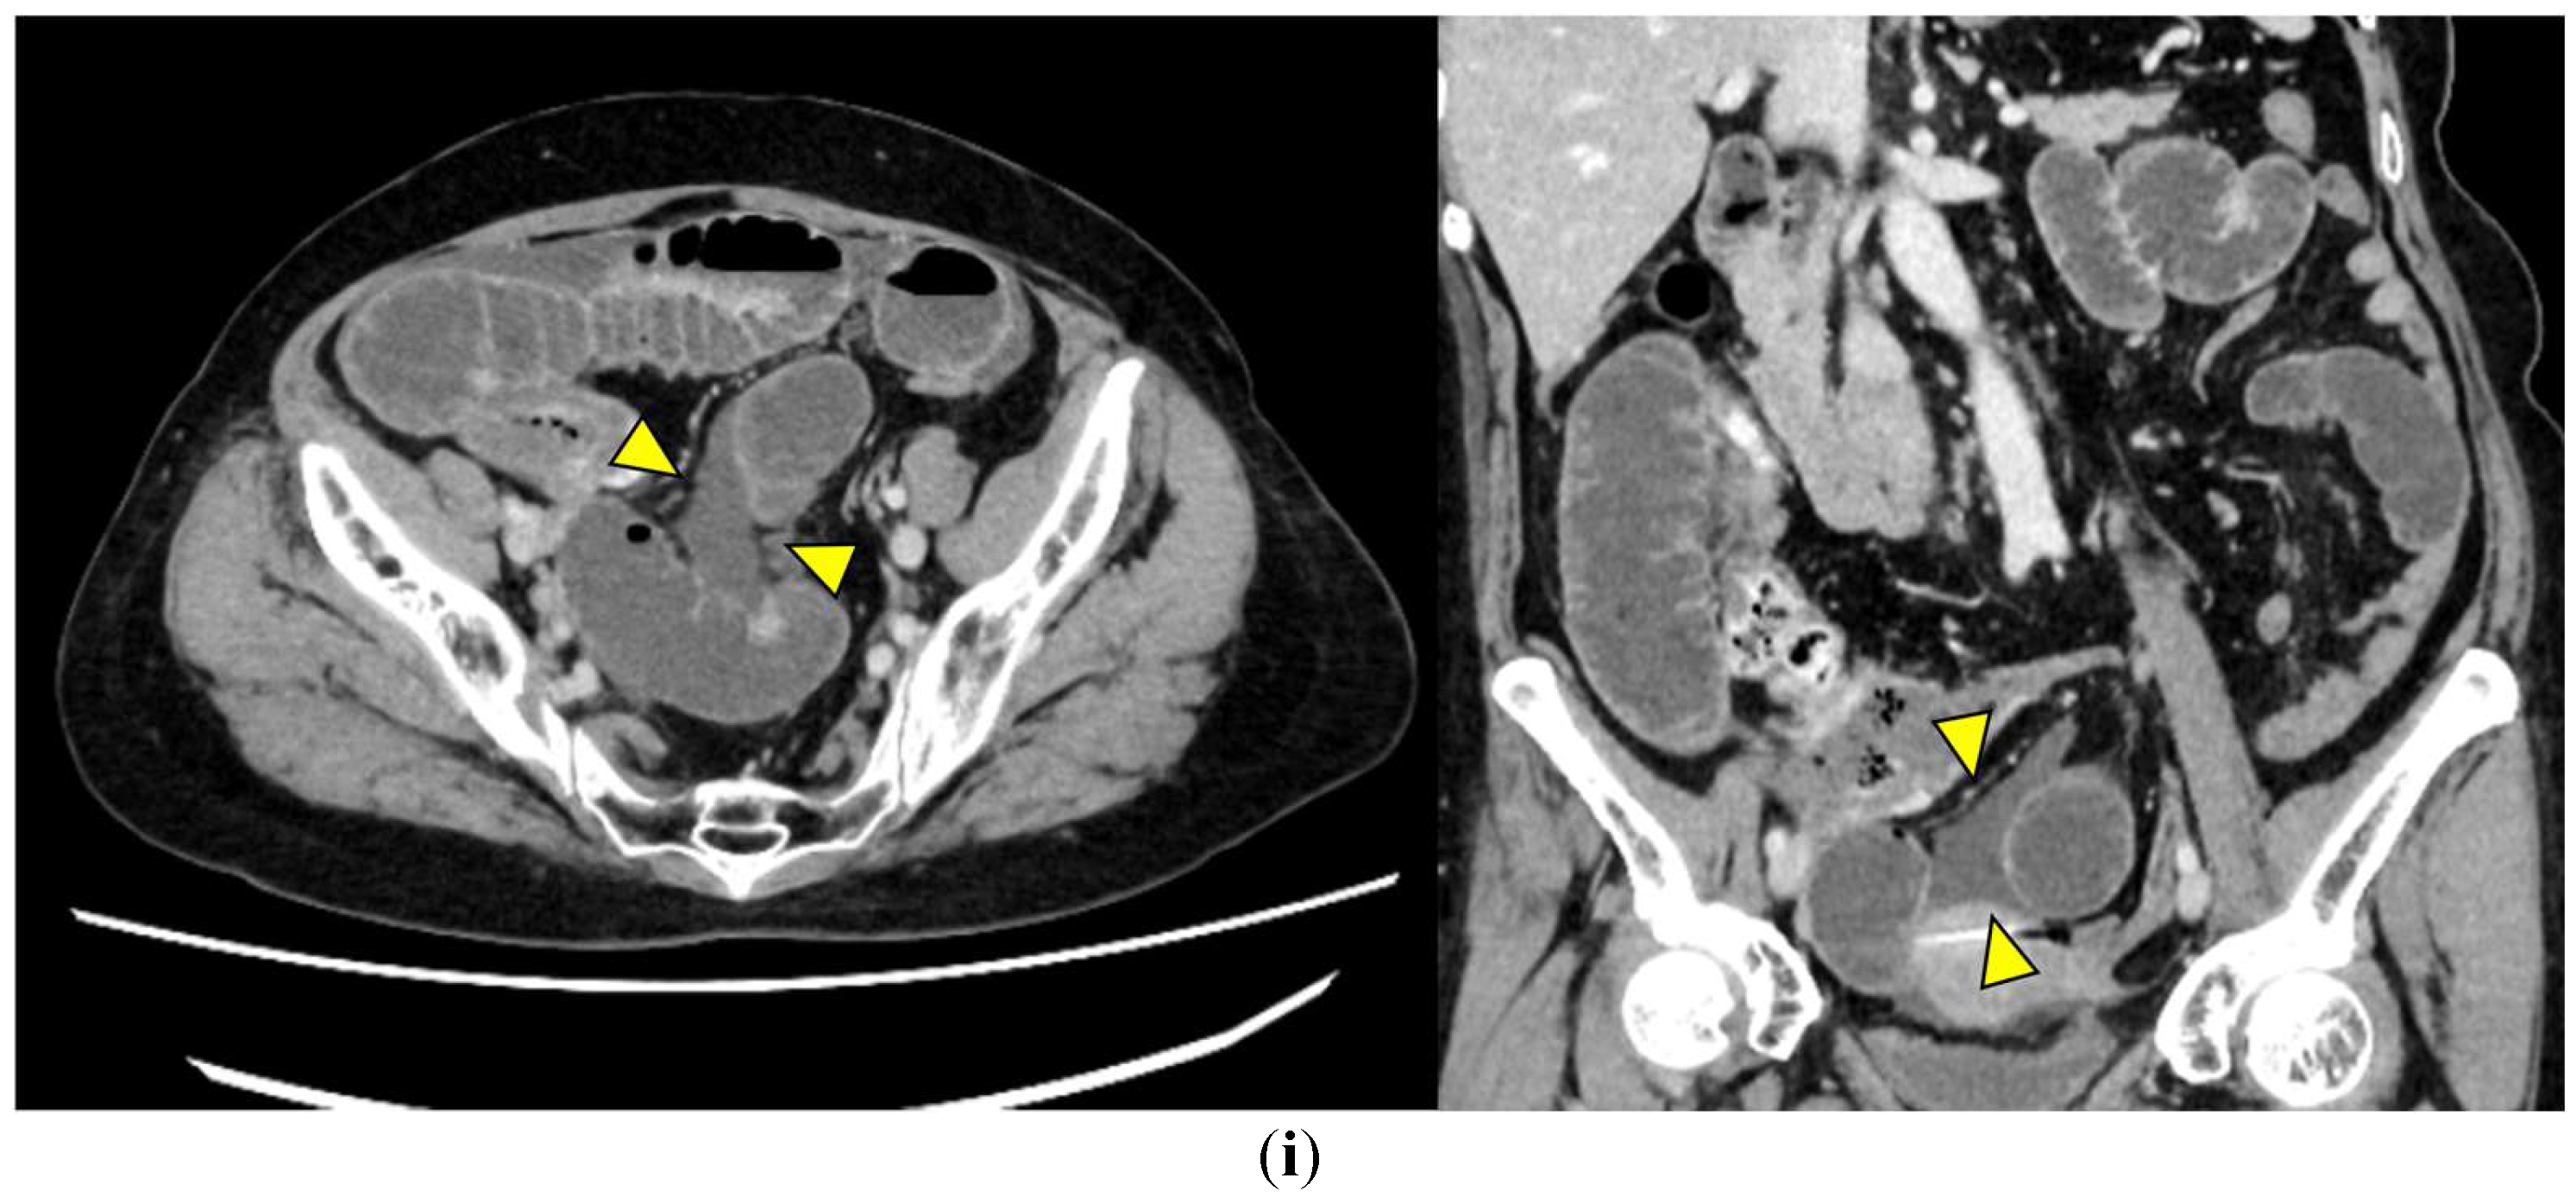

Representative images are presented in Figure 1.

• Closed loop (Figure 1a): A dilated U- or C-shaped bowel segment with two transition points in close proximity, often associated with radial distribution of mesenteric vessels. This configuration may carry a high risk of rapid progression to strangulation and ischemia, requiring prompt surgical consideration.

• Beak sign (Figure 1b): Gradual tapering of the bowel lumen or contrast column at the obstruction point, typically indicating torsion or sharp angulation. This sign localizes the obstruction and often reflects mechanical blockage due to adhesions or volvulus, which may progress to ischemia if left untreated.

• Whirl sign (Figure 1c): Swirling of mesenteric vessels and fat, suggestive of volvulus or twisted mesentery. Presence of this sign strongly suggests torsion with compromised mesenteric blood flow.

• Small bowel feces sign (Figure 1d): Mixture of gas and particulate matter (resembling feces) within a dilated small bowel loop proximal to the obstruction, indicating delayed transit. This sign indicates subacute or prolonged obstruction, but does not necessarily imply ischemia.

• Mesenteric edema (Figure 1e): Increased attenuation and stranding of mesenteric fat surrounding the affected loop, typically reflecting venous congestion. This is an early indicator of impaired venous outflow and increased risk of ischemia, requiring close monitoring and a low threshold for surgical intervention if clinical deterioration occurs.

• Mesenteric vessel engorgement (Figure 1f): Prominent or dilated mesenteric veins near the involved segment, suggestive of impaired venous outflow or strangulation. Venous congestion typically precedes arterial compromise, and the presence of this sign indicates evolving mesenteric ischemia.

• Absent bowel wall enhancement (Figure 1g): Complete absence of bowel wall enhancement on contrast-enhanced CT, which is highly suggestive of transmural infarction. This is a critical sign of irreversible ischemia and generally indicates the need for immediate surgical intervention.

• Blurred Kerckring folds (Figure 1h): Indistinct mucosal folds (valvulae conniventes) in dilated small bowel loops, often associated with ischemic edema. Blurring of mucosal folds reflects mucosal/submucosal injury from ischemia and impending bowel damage due to severe obstruction.

• Ascites (Figure 1i): Free peritoneal fluid, either localized around the affected loop or diffusely distributed, is frequently associated with advanced ischemia. Increasing ascites in the obstruction setting often indicates transmural ischemia or severe inflammation.

Figure 1. Representative CT findings suggestive of SSBO. Yellow arrowheads highlight the relevant findings. (a) Closed loop; (b) beak sign; (c) whirl sign; (d) small bowel feces sign; (e) mesenteric edema; (f) mesenteric vessel engorgement; (g) absent bowel wall enhancement; (h) blurred Kerckring folds; (i) ascites.